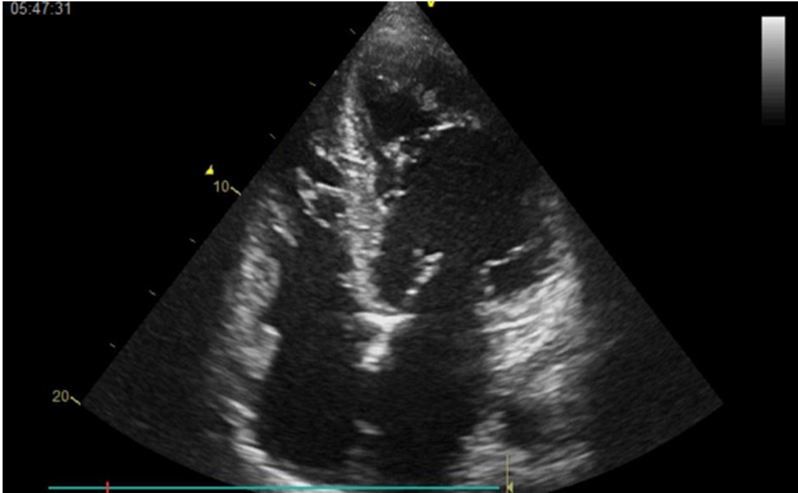

Echocardiography confirmed a severely depressed left ventricular ejection fraction (LVEF) of 20%, with a markedly dilated left ventricle, prominent trabeculations, spontaneous echogenic contrast, and an apical thrombus—all features raising suspicion of a left ventricular non-compaction cardiomyopathy (LVNC) (figure 2 and 3)

Figure 2: 4 cavity echocardiography showing the left ventricle trabeculations